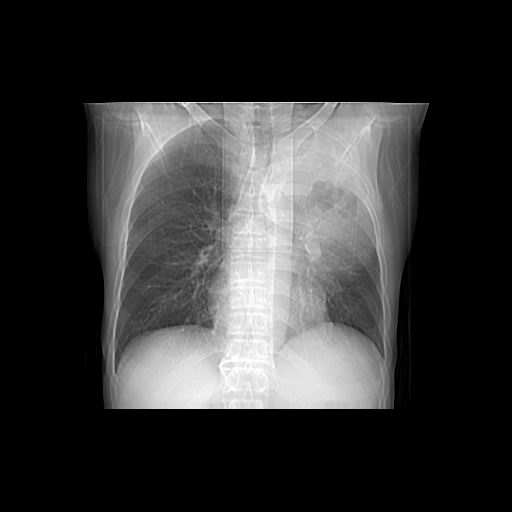

以下是引用杀毒软件在2009-4-28 17:58:00的发言:[br]考虑----左肺慢性肺脓肿形成继发上叶含气不良---抗炎后复查---待排肿瘤所致[br][br][本贴已被 杀毒软件 于 2009-4-28 18:01:26 修改过]